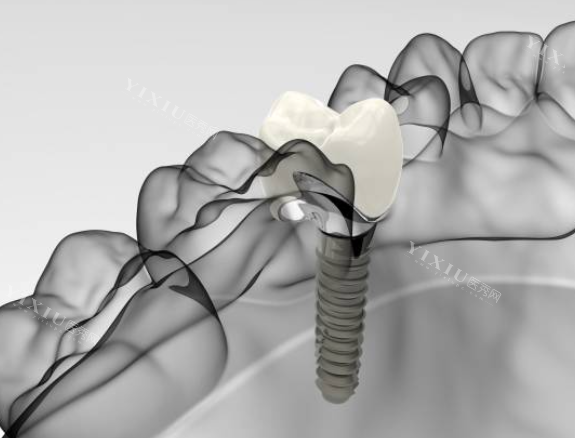

卡尔斯种植牙采用4级冷作钛材质,这种材料具有良好的生物相容性。其表面经过改良的SLA工艺处理,形成微米级粗糙表面,有利于骨组织结合。双向螺旋式切刃设计是该产品的特色之一,这种结构有助于提高初期稳定性,同时能加速骨结合过程。

ITI(士卓曼)种植体在材料选择上更为多样化,包括纯钛和钛锆合金等不同材质。表面处理技术是其一大亮点,如SLActive亲水表面技术能够促进早期骨结合,缩短愈合时间。部分特殊型号的设计特别适合骨量不足的情况或即刻种植的需求。